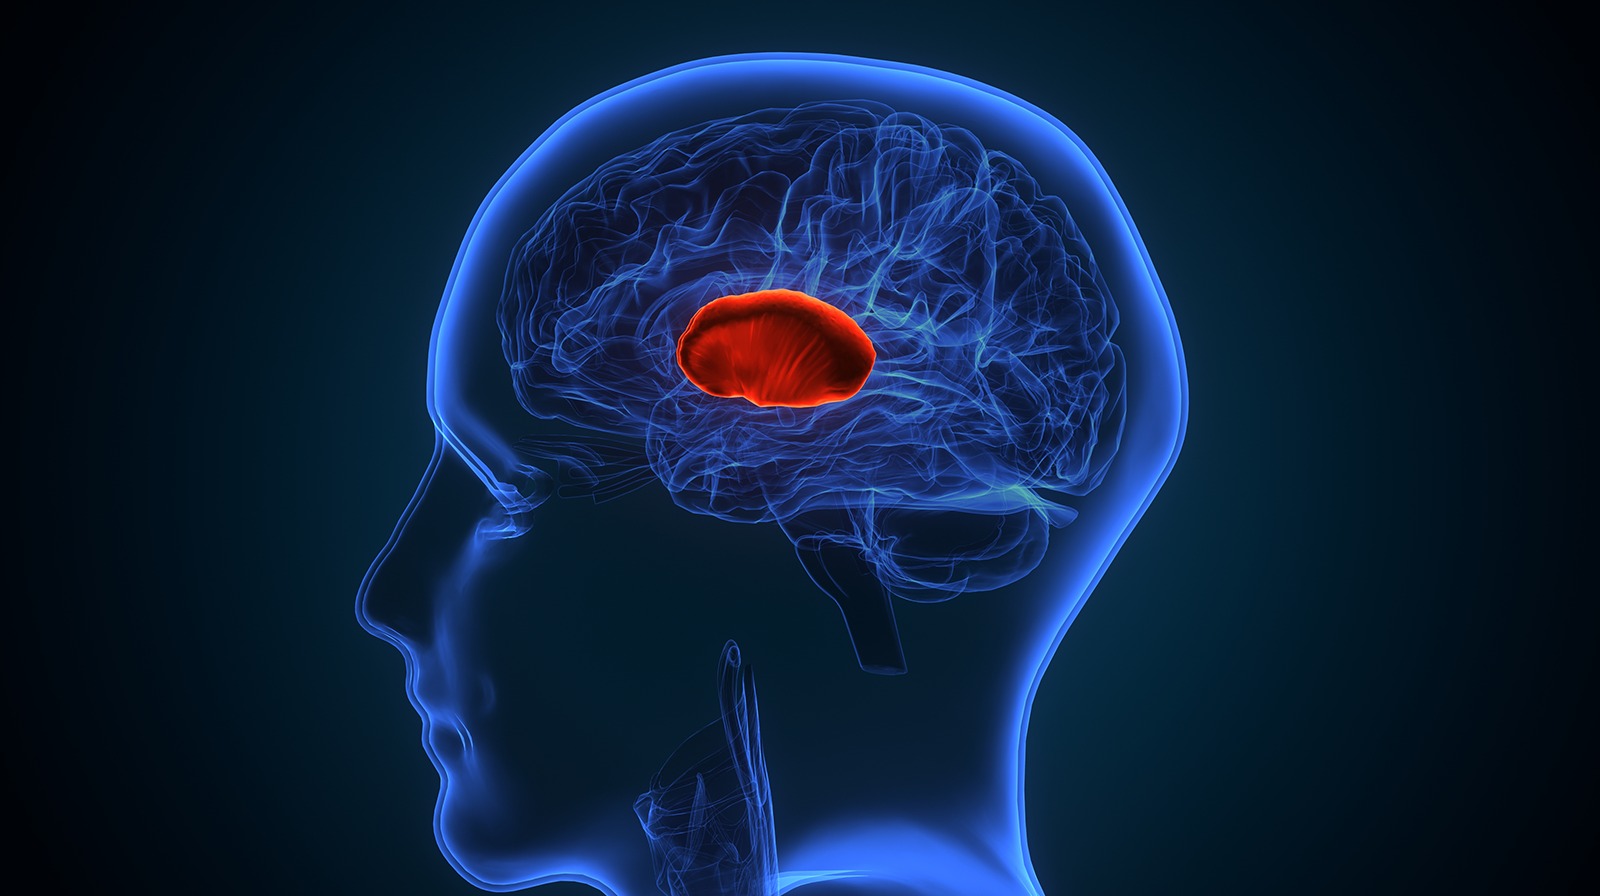

Blood Clots in the Brain: Early Symptoms, Diagnosis, and Medical Care

Have you ever had a sudden, splitting headache that came out of nowhere? Or maybe you felt quite dizzy, not able to speak clearly, or had weakness on one side of your body? These may seem like random symptoms, but

What is a Brain Stroke? Types, Symptoms and Causes

Introduction A brain stroke is a serious medical condition that can have life-altering consequences. Understanding its different types, stroke symptoms and their causes is crucial for prevention and early treatment.In this blog, we will dive into what a brain stroke

Blood Clots in the Brain:

Have you ever had a sudden, splitting headache that came out of nowhere? Or maybe you felt quite dizzy, not able to speak clearly, or had weakness on one side...

What is a Brain Stroke?

Introduction A brain stroke is a serious medical condition that can have life-altering consequences. Understanding its different types, stroke symptoms and their causes is crucial for prevention and early treatment.In...